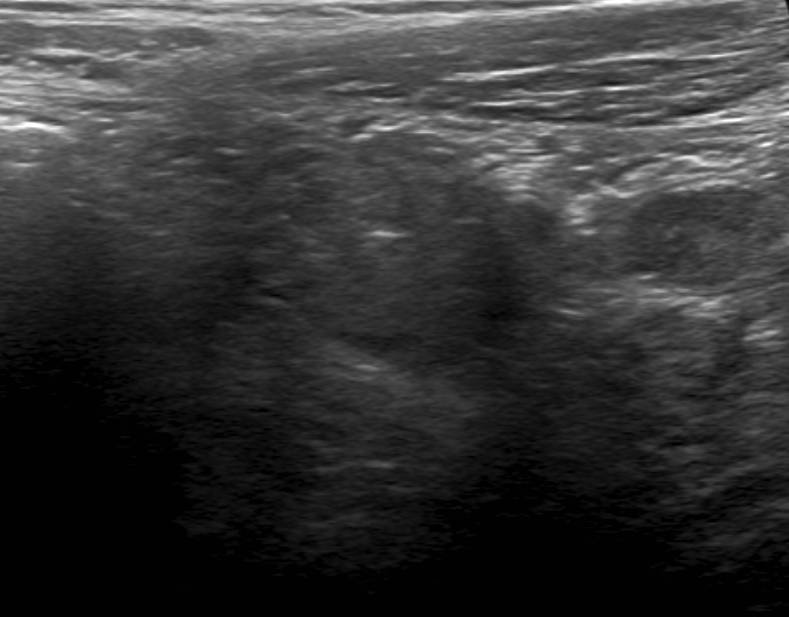

Ultrasound is a fast and cost effective option for analysis of potential appendicitis. It can be performed at the bedside if necessary, and no radiation is involved.

Because of gas obscuring the appendix on ultrasound, a CT is required to assess this case. A CT with contrast is preferred where possible. It will help with assessment of an inflamed appendix.

Socioeconomic Factors: The diagnosis of appendicitis can often be made by ultrasound, especially in the pediatric population. It would be lower cost and there is no radiation exposure. However, the appendix may be obscured by bowel gas and a CT would be necessary if clinical suspicion remains high.